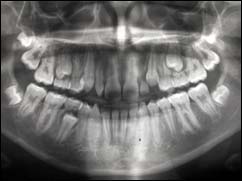

Cette radio permet d'appréhender l'ensemble de votre dentition et des structures adjacentes.